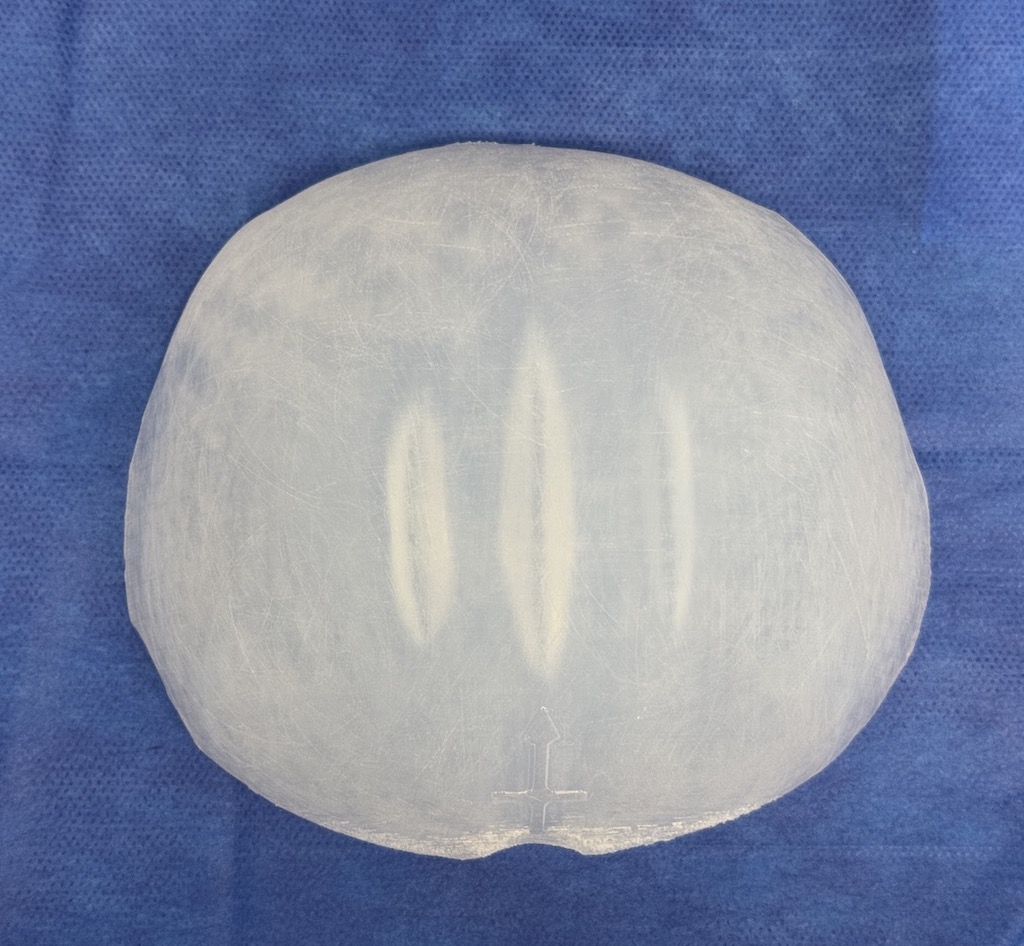

Desire for further skull augmentation after a primary skull implant.

Five years after an initial custom skull implant placement a new custom skull implant that increased the volume by 35% was placed.

Desire for further skull augmentation after a primary skull implant.

Five years after an initial custom skull implant placement a new custom skull implant that increased the volume by 35% was placed.